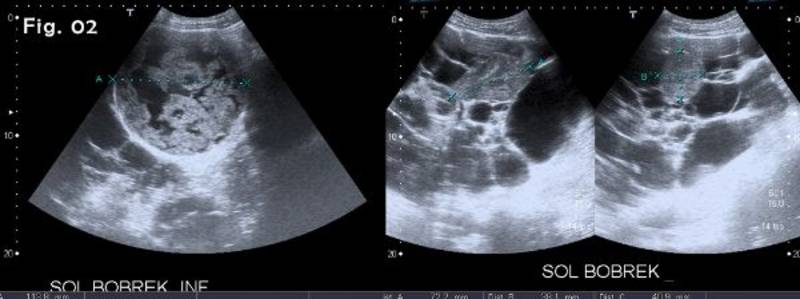

Kreisā nierē papildus tika atrasta arī kompleksa cistiska masa 114 mm diametrā un blīva masa, kuras izmēri bija 72x41x38 mm (2. attēls).

Krāsu Doplera izmeklējumā blīvā maisa bija bagātīgi vaskularizēta (3. attēls). Kompleksajā cistā vaskularizācija netika novērota.